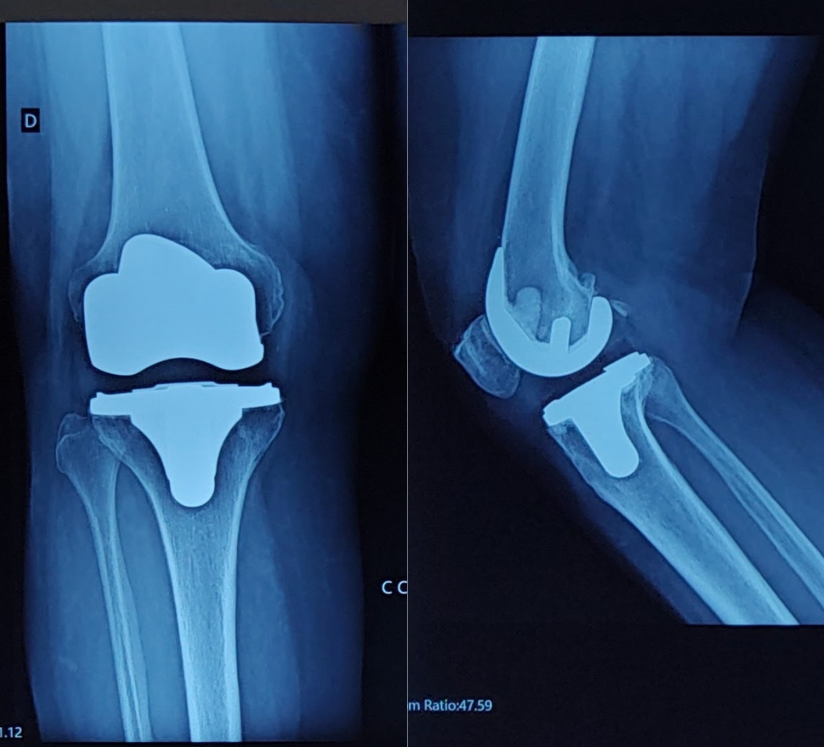

Ilustração de artroplastia de joelho

No caso do joelho, a artroplastia pode ser parcial, quando apenas uma parte da articulação é substituída, ou total, quando toda a articulação é substituída por componentes artificiais que reproduzem o movimento natural do joelho.